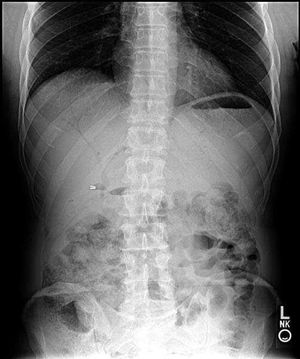

Diagnosis?

Pneumobilia, bilioenteric fistula

Pneumobilia

The air under the left part of the diaphragm coused by ruptured gastric ulcer.

Good observation; that looks like the fundus of the stomach. Normal finding